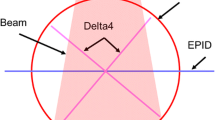

The necessity for quantitative evaluation of competing measurement devices, in cases where on device has not been found to be superior, is a significant need in science generally [1, 2, 5–7], and particularly within the radiological sciences community. Specifically, this issue is encountered when comparing distinct positional verification methods for image-guided radiotherapy [34, 53–56]. The difficulty of assessing competing platforms is particularly vexing, as it impedes efforts at cross platform comparison. Our group [24, 50] and others have implemented several distinct methods for presenting such analysis [25, 27, 33, 34, 45, 57]. Our previous efforts have utilized several extant method comparison statistical presentations (including Bland-Altman7, Lin’s concordance [58], Deming orthogonal regression [59, 60]); however, what was gained in completeness was lacking in parsimony. To this end, we sought to define an improved algorithm for practical comparison of distinct imaging methodologies, with a non-fixed number of repeated measurements per patient, in the absence of a “gold standard”. Often, inappropriate statistical analyses are implemented in lieu of formal method comparison statistics. The analysis of different measurement devices is not as straightforward as the initial observer may suppose. Bland and Altman demonstrated that mean comparison and linear regression are insufficient for comparison of differing measurement techniques [1]. The Bland- Altman method is succinct and easily interpretable, making it a classic of medical literature. In a series of seminal papers [1–7], Bland and Altman defined the standard methodology for comparing differing measurements, as well as establishing effective techniques accounting for inter- and intra-method variability/repeatability. However, while the Bland- Altman methodology remains the current benchmark, it fails (by design, one should note) to include generation of a formalized p − value, instead recommending that a clinically meaningful difference between measures be utilized. Additionally, though repeatability estimation is a recommended component of accurate method comparison, the calculation for greater than two replicates is somewhat unwieldy using the methodology proposed by Bland and Altman. Since many IGRT datasets span > 30 repeated daily measures, the utility of a statistical methodology which can readily integrate large replicate numbers is desirable. The COM3PARE methodology presented herein represents an attempt to integrate several desirable methodological attributes into a unified, readily performed statistical process. COM3PARE has several advantages over existing method comparison statistical analyses. Specifically, compared to general linear model [61, 62] (GLM)-based approaches (such as the t-test, linear regression, and ANOVA [63]), which fail to account for multiple sources of random variance, the linear mixed effects (LME)-based COM3PARE platform integrates variation estimation at multiple hierarchical levels (i.e., between- and within- measurement methods/subjects) [48]. From a practical point of view, this allows factor-wise assessment of procedural or technical variability of each of the two methods rather than a combined assessment, so that there is the capacity to determine the exact source of disagreement. COM3PARE is also resilient with regard to uneven numbers of replicates per device, a feature of great practical utility in a clinical setting, such as daily IGRT recording, where the number of IGRT fractions received for each patient may differ based on fractionation regimen of clinical exigency. Additionally, since COM3PARE has the capacity to fit differences in said variability to a hypothesis testing-friendly Bonferroni-corrected p − value output, while still implementing clinician-determined thresholds for agreement there is greater interpretability of statistical output, with no loss of clinical relevance. For instance, one could specify a priori that measurement differentials >1 mm would represent a lack of interchangeability globally. Data presentation was performed in this study in an effort to illustrate potential applications of COM3PARE for replicated image-based measurements of the kind frequently encountered in radiation oncology. The specific dataset included have been previously presented using standard method approaches. By revisiting these data using compare we hope to illustrate implementation of what we perceive to be a more usable and parsimonious approach to conceptualizing method comparison for IGRT applications, expanding upon, rather than obviating the previous work. With regard to the specific dataset presented herein, our analysis points to the difficulties possible when comparing IGRT platforms. For instance, having set our criteria pre-analysis, we were surprised to note that differing measurement methods proved preferable in distinct axes (e.g., CBCT in X-axis, kV X-ray for the Z-axis), while appearing by said criteria interchangeable in the Y-axis. A possible explanation of this phenomenon may appear as a feature of the imaging methodologies themselves. For CBCT, before three-dimensional reconstruction, data is acquired as axial slices (X-axis), while, previous to DRR referencing, the kV X-ray system uses orthogonal projections at oblique angles, parallel to the superoinferior plane (Z-axis). Consequently, method intra-subject repeatability may be tied to the reference plane of image acquisition, though this remains conjecture based on a single dataset. To our knowledge this technique represents the first formal hypothesis testing approach to integrate inter-method bias, inter-subject variability, and intra-subject variability of two methods with any number of replicated measurements for image-guided radiotherapy. As modeled on the aforementioned conceptual schema presented in the “Methods” section, we postulate that the following criteria be formally evaluated as feature of future image-guided radiotherapy measurement comparison studies comparing two imaging platforms, where multiple repeated observations on the same subject is possible. To meet our criteria for interchangeability [48]:

These criteria are presented as a graphical schema (Fig. 1); notably analysis of criteria 1–3 is easily incorporated in a single step using the COM3PARE SAS Code (Appendix A). The a priori criteria set we specified for interchangeability represented what we considered a reasonable metrics for the given application (i.e. fractionated radiotherapy of 30+ fractions for head and neck cancer) with a standardized PTV margin. The COM3PARE methodology, however, allows specification of any specified difference/p-value combination. Consequently, if a scenario arose whereby either tighter tolerances are desirable (e.g. 3-fraction SBRT), such parameters can be easily defined as an acceptability criteria.